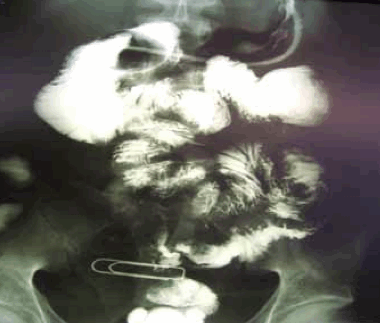

При наружных свищах проводится фистулография (введение контрастного вещества в свищ). Следует уделить внимание обязательному попаданию контраста в отводящую петлю с целью выяснения скорости пассажа контрастного вещества по кишке, обнаружения его задержки и определения уровня этой задержки. Данная информация имеет значение для хирургического вмешательства, при котором необходимо ликвидировать сам свищ, а также перегибы и деформации отводящей петли. Это позволит избежать гипертензии в области швов анастомоза в послеоперационном периоде.

При внутренних свищах осуществляется введение контрастного вещества через рот.

При наружных свищах контрастирование через рот также необходимо для выяснения состояния приводящей петли свища - ДПК и/или желудка.

Для оценки состояния внутренних органов, взаимоотношения их со свищевым ходом может потребоваться УЗИ органов брюшной полости, мультисрезовая спиральная компьютерная томография органов брюшной полости, обзорная рентгенография органов брюшной полости. Также широкое применение нашли рентгенконтрастные методики: рентгенография пассажа бария по тонкому кишечнику, ирригоскопия, фистулография (введение контраста в свищевой ход).

- Фистулография. Является наиболее распространенным визуализационным методом диагностики наружных свищей. Контраст вводят в отверстие, по данным снимков определяют пораженный орган, точную локализацию фистулы, направление хода, наличие затеков.

- Рентгенография с контрастированием. При внутренних поражениях проводят ирригографию, рентгенографию желудка или пищевода с барием. Контраст выходит через стенку органа на кожу, в соседние органы или полости, что позволяет уточнить особенности свища.